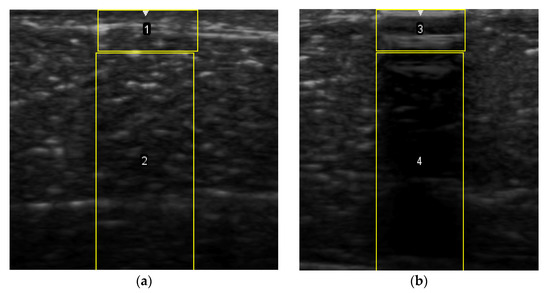

2.6. Echogenicity

To measure the echogenicity of each aerogel type, two ROIs were strategically selected from each B-mode image and indicated with a clear boundary in Figure 3. These correspond to top ROI which represents the implant area and bottom ROI representing the posterior shadowing region. Figure 3a shows these two regions in the absence of any aerogel implants while Figure 3b captures the same regions in the presence of an implant (ROI-3 and ROI-4). In each case, the Mean Pixel Intensity (MPI) of the two ROIs was measured using the measure function in ImageJ. MPI of ROI-1 and ROI-2 formed the baseline for the percentage change calculation, which was arrived at using Equation (4a,b)—Table 2. Based on the value of the ROI, aerogels were classified as hyperechoic, isoechoic, hypoechoic, and anechoic and summarized in Table 3 where ΔE can vary between −100% and +255%. Acoustic impedance mismatch between the aerogels and tissue was calculated using a percentage difference method, indicated in Table 2 by Equation (6).

Figure 3.

(a) Selection of ROI-1 and ROI-2 in the B-mode image of the muscle without implants. (b) Selection of ROI-3 and ROI-4 in the B-mode image with aerogel implants.

To calculate the standard error of the mean, the MPI of each ROI was collected from three (N = 3) different images for the same frequency and for the sake of consistency all the same device settings were used.